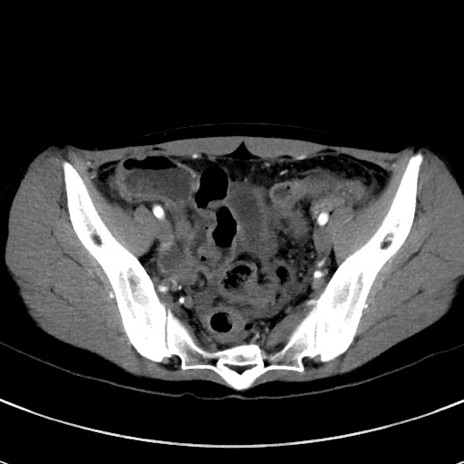

症例17(横断像)

【症例】20歳代女性

【主訴】嘔吐、下腹部痛

【現病歴】昨日夕食後に嘔吐し下腹部痛が出現。本日になっても嘔吐持続し改善しないため来院。

【身体所見】意識清明、BT 37.2℃、BP 108/67mmHg、腹部:平坦、やや硬、下腹部正中から右にかけて圧痛あり、反跳痛軽度あり、tapping pain(+)。

【データ】WBC 13600、CRP 14.94